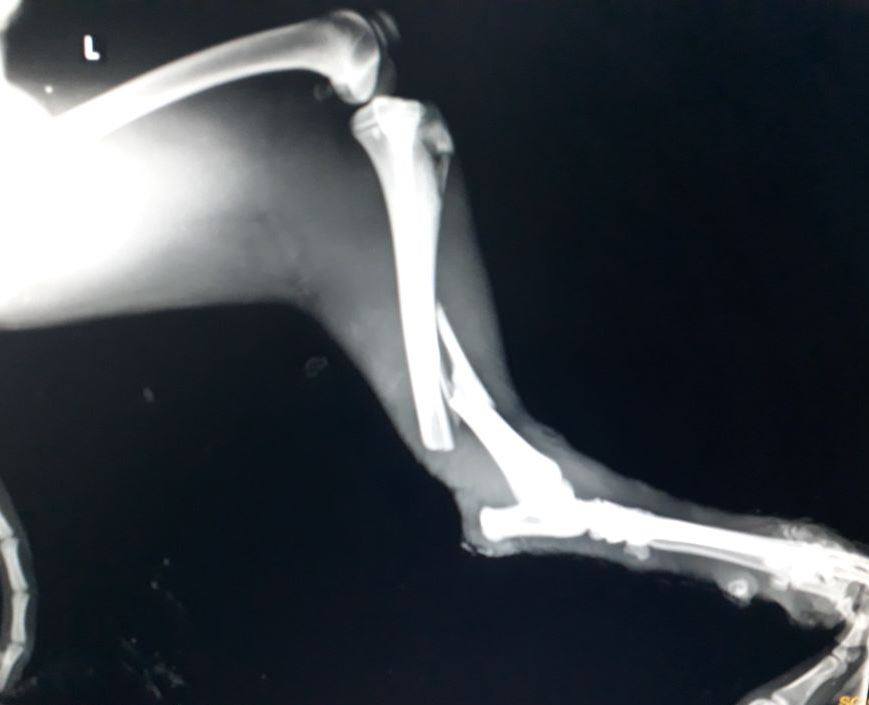

My x-ray report clearly explained tibia and fibula fracture of my left hind limb. My limb is swollen giving rise to unexplainable pain. The doctor at the shelter has already started my treatment and I truly want to walk normally again.